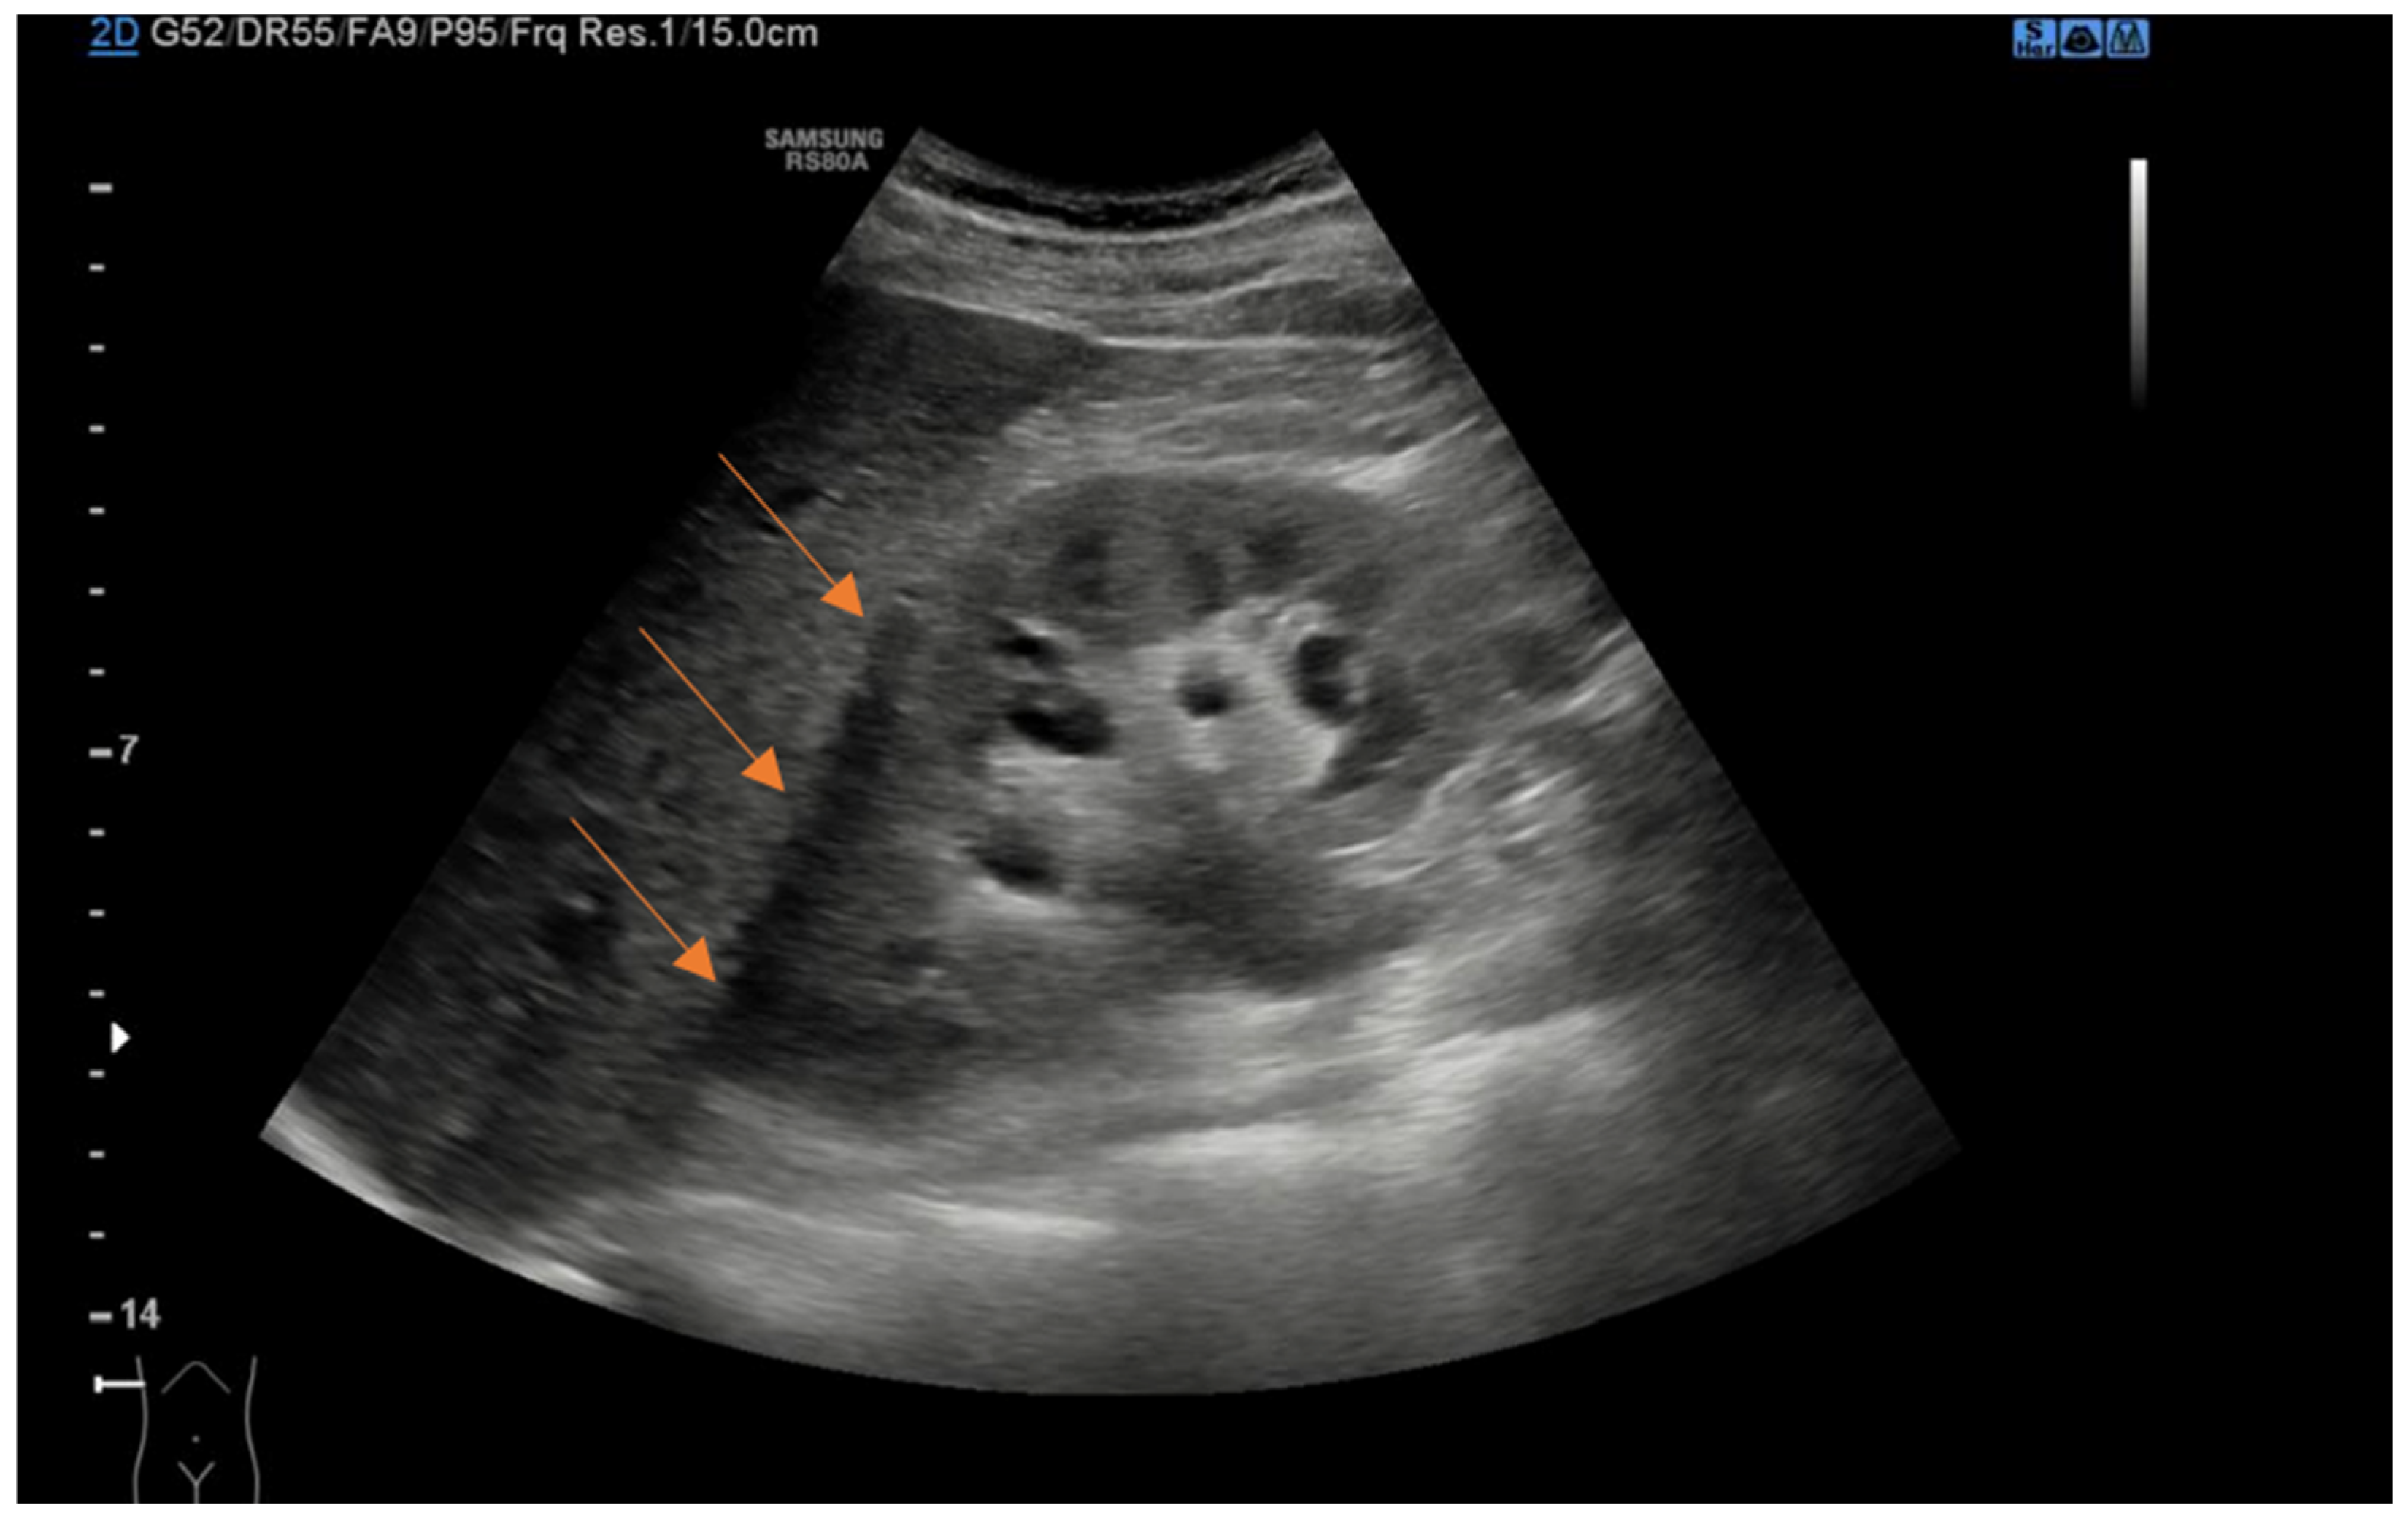

Figure 1.

Coronal ultrasound view of right kidney demonstrating anechoic perinephric fluid (arrows).

We retrospectively collected data from patient charts, which included baseline demographic and clinical characteristics such as age, sex, body mass index (BMI), comorbidities, previous history of kidney stones or renal colic, initial presentation symptoms, and the presence of fever. Clinical and laboratory data at the time of ED presentation were also recorded, including the diameter of the kidney stones in millimeters, stone location, presence of perinephric fluid, presence of hydronephrosis, and laboratory findings such as creatinine level and leukocytosis, which provided information on renal function and potential infection. Using a curvilinear probe, experienced US radiologists examined the urinary system with a Samsung RS80A US machine. Perinephric fluid was defined as any anechoic stripe within the perirenal space bordered by the renal parenchyma and Gerota’s and Zuckerkandl’s fasciae, not including the anterior or posterior pararenal spaces, or the subcapsular space (Figure 1) [17]. The presence of hydronephrosis was defined as renal pelvic/calyx dilatation. The severity of hydronephrosis was defined according to the renal pelvic diameter (mm): 0–10 mild, 11–20 moderate, and >20 severe. Patients with hydronephrosis upon US without evidence of the cause of obstruction underwent a CT scan to evaluate the presence of a ureteral stone not visible with the US. Additionally, treatment-related data were gathered, including whether patients were discharged home or required hospitalization from the ED, the specific type of intervention performed (such as medical expulsive therapy, ureteral stent placement, nephrostomy tube insertion, or retrograde intrarenal surgery), and the length of hospital stay. For patients with favorable clinical conditions and ureteral stones less than 10 mm, we opted for conservative management and initiated medical expulsive therapy. These patients were discharged from the ED with instructions to return if they experienced recurrent renal colic that did not respond to analgesic therapy or if they developed a fever. Otherwise, they were scheduled for a follow-up urology visit 2 weeks after ED discharge, which included US and bladder exams. Patients with recurrent colic, not responsive to analgesic therapy, or patients with signs and symptoms of infections or compromised renal function were generally treated with immediate surgical intervention, which involved stent or nephrostomy placement, or ureteroscopy when feasible.